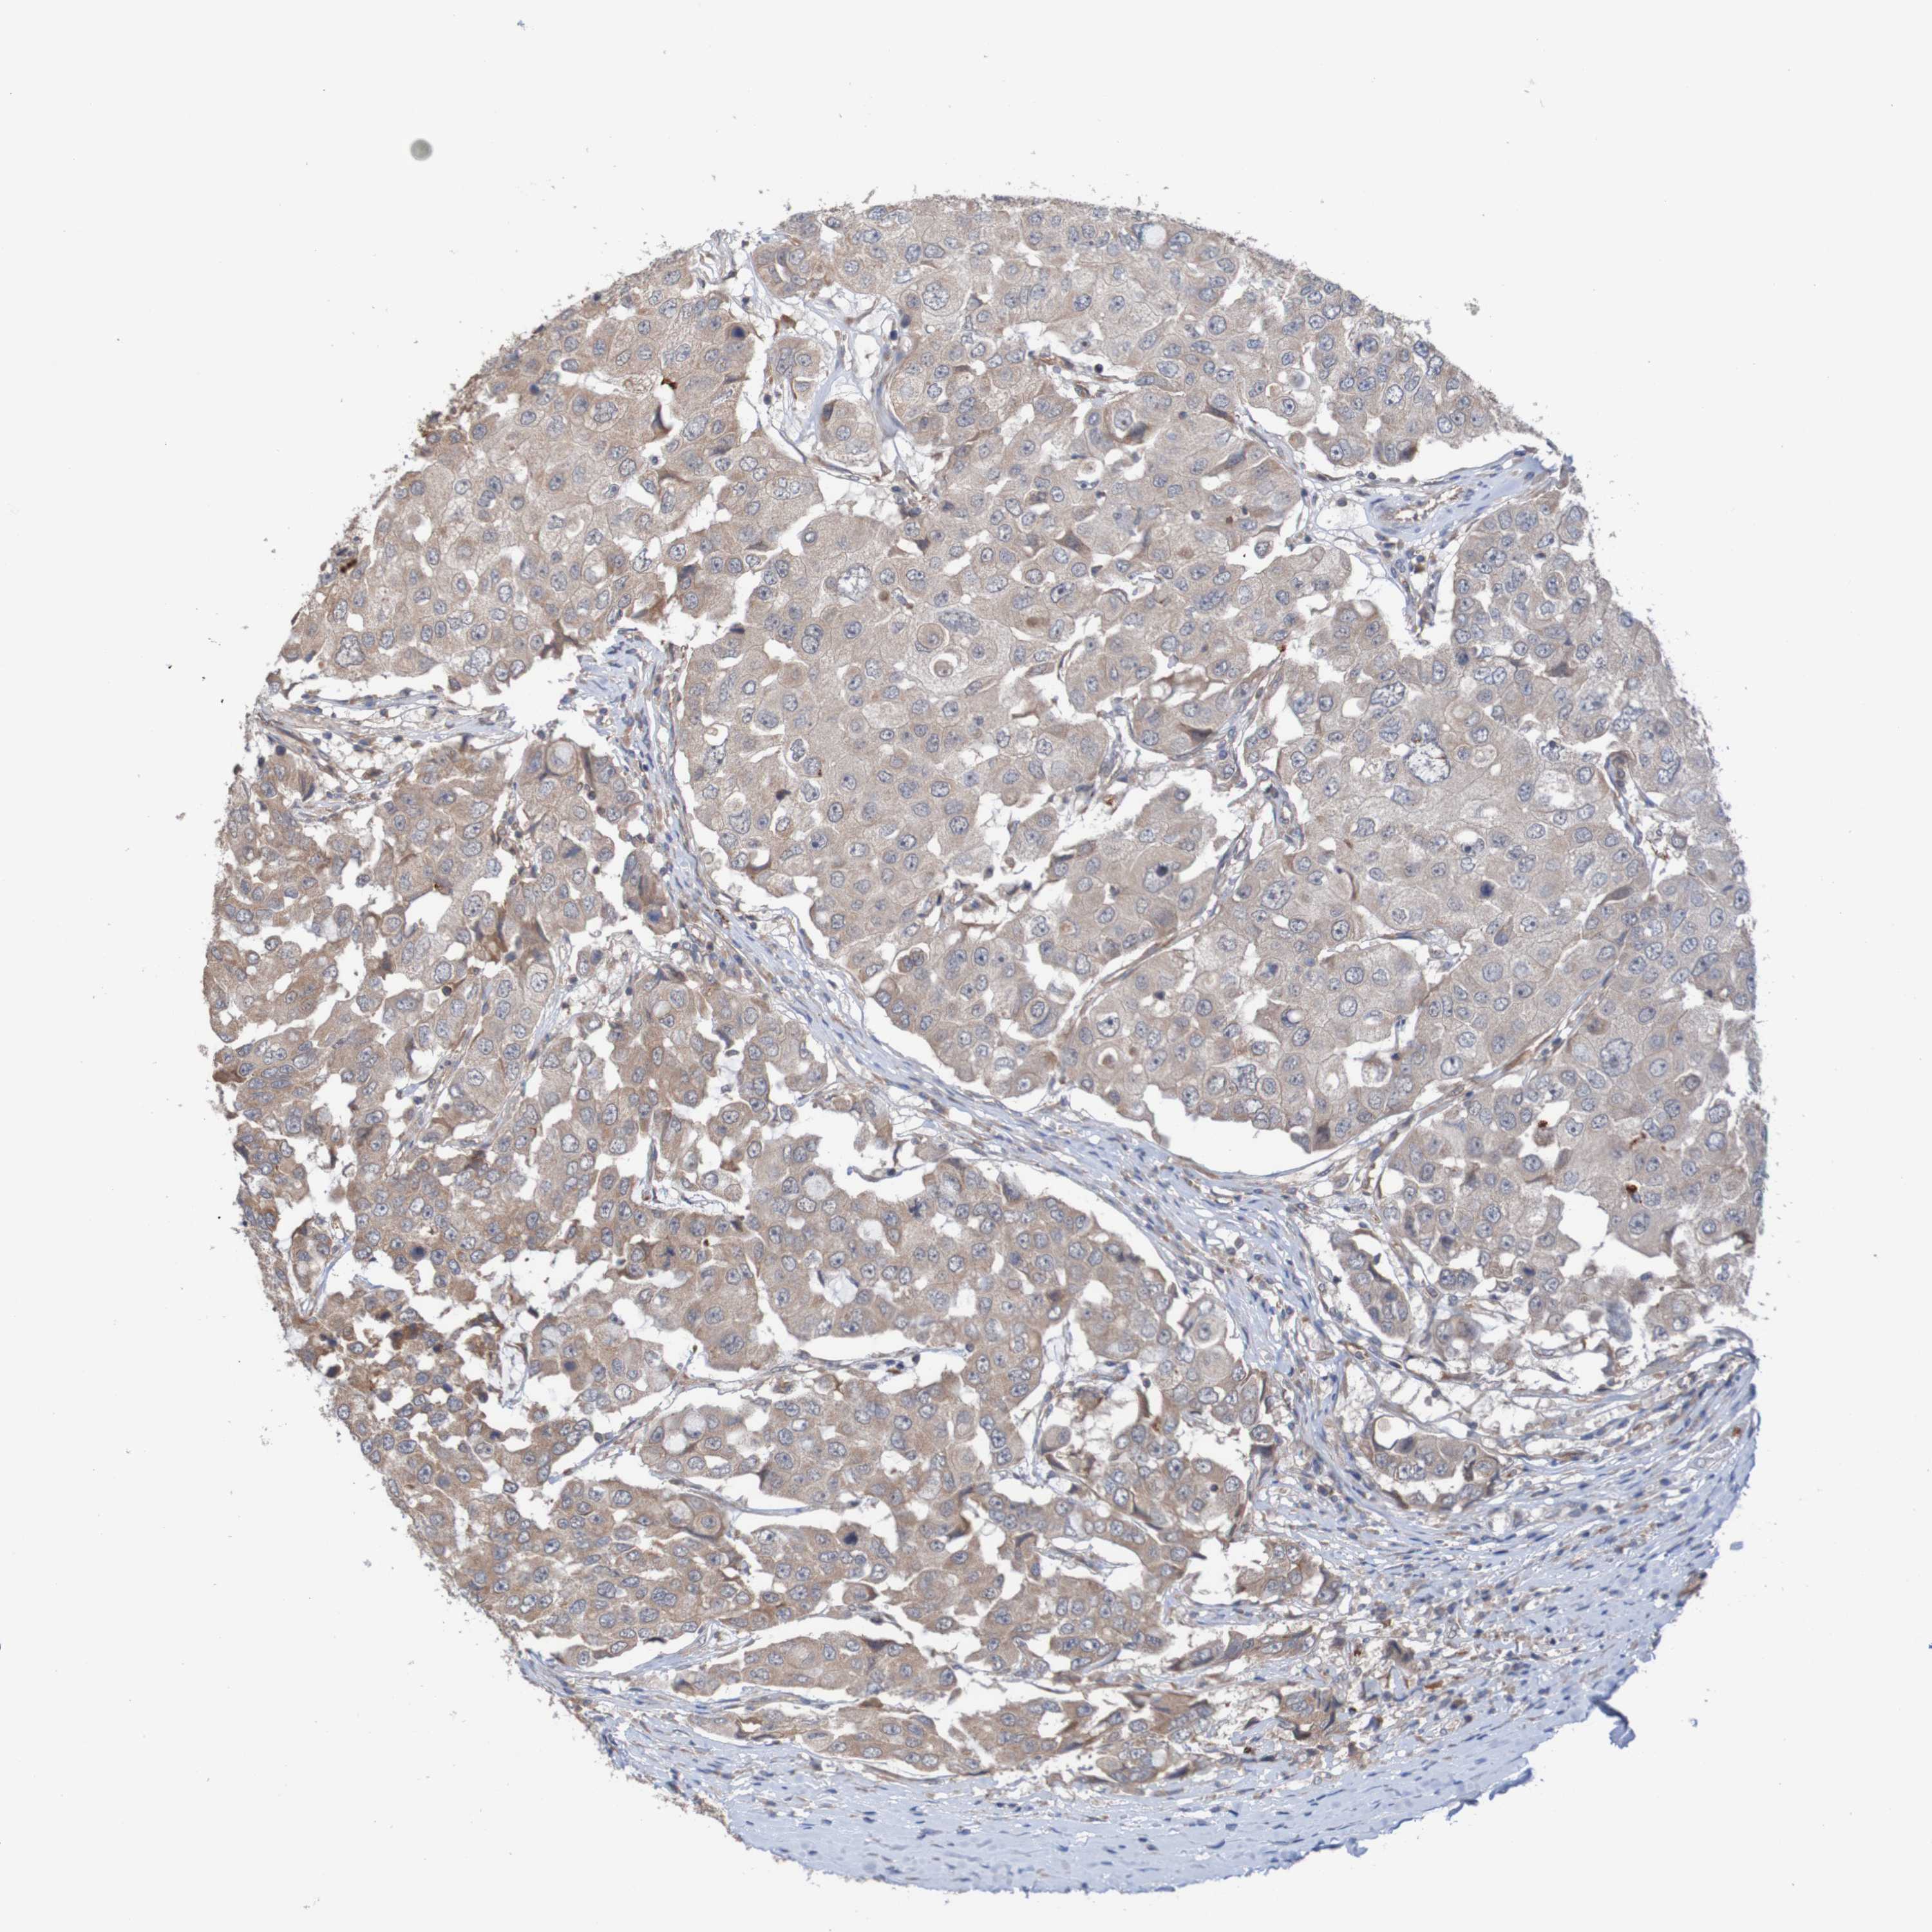

CANCER BREAST CANCER Show tissue menu

BRCA TCGA BRCA VALIDATION PROTEIN EXPRESSION